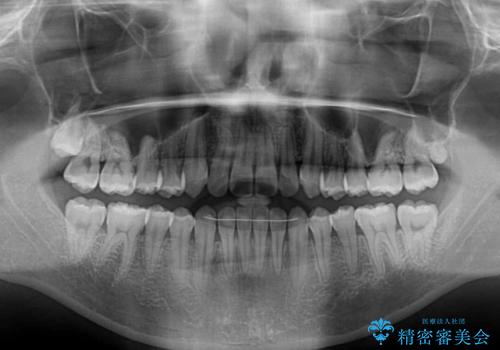

前歯のデコボコが早めに改善され、スムーズに治療を終えることができました。

- 前歯のデコボコを気にして来院された患者様です。

歯列としてはワイヤー装置でもインビザラインでも対応可能でしたが、インビザラインが苦手とする上顎側切歯(真ん中から2番目の歯)の舌側転位が顕著でした。

治療の確実性を上げるために、インビザライン開始前に上顎のワイヤー装置にて舌側転位を解消し、その後インビザラインにて矯正治療を行うこととしました。